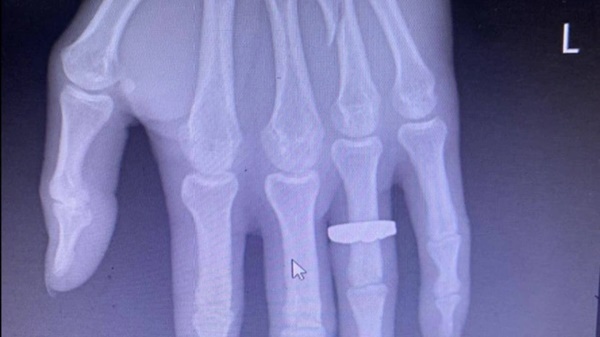

Hình ảnh xương ngón tay áp út bàn tay trái của anh Sáng bị đánh gãy.

Anh Sáng được các y, bác sĩ Bệnh viện Đa khoa Bãi Cháy bó bột do gãy ngón tay áp út của tay trái.